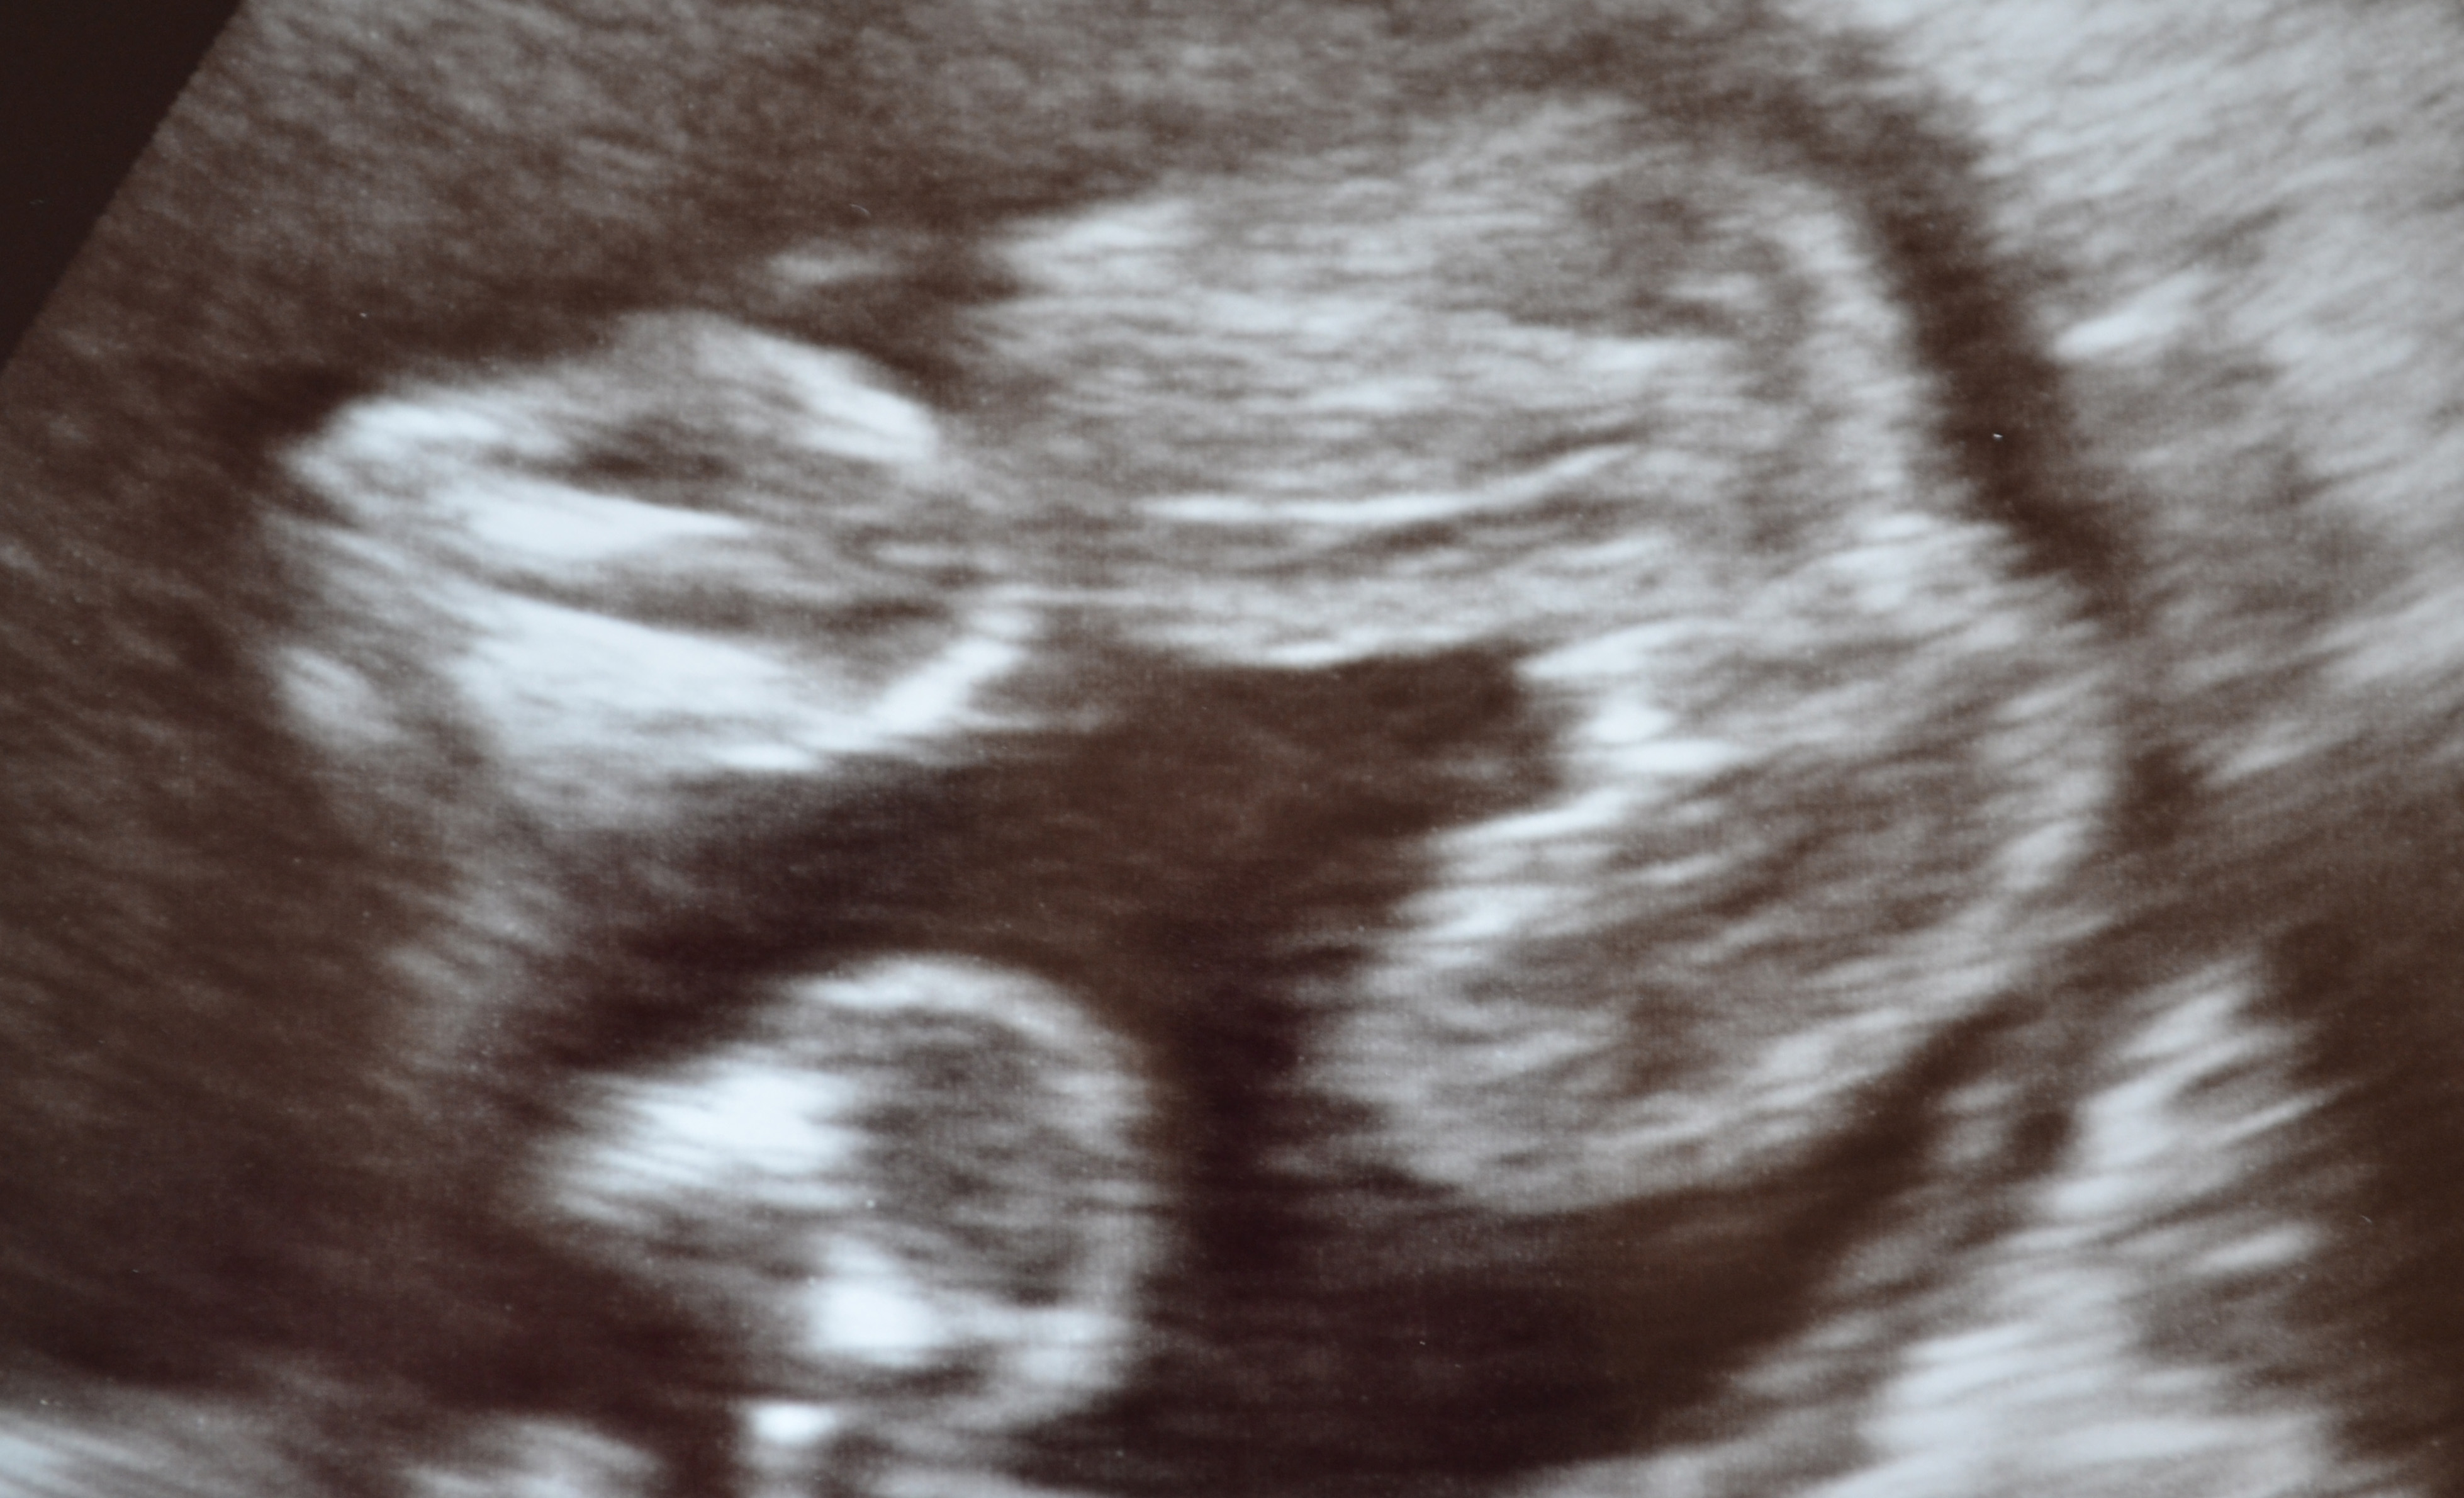

Hello everyone, i am new here and looking forward to joining everyone i went for a 20 week private ultrasound scan and was told 100% girl and the tech seemed pretty confident and showed us why she was certain it was girl etc NOW my problem is when i went for my anomoly scan at my local hospital the girl told me that normally the private techs aren't usually well trained :rolleyes: but the hospital aren't allowed to tell the sex so she was no help!!

Also 3 people have said to me 'oh be careful I was told girl and out came a boy' now im really worrying as i have bought so much stuff etc.... I will post my potty shot, some others have said oh the penis could floating upwards so thats why it looks this way.. please put me out of my misery and save me a small fortune as im tempted to go back!!! xxAttachment 4108